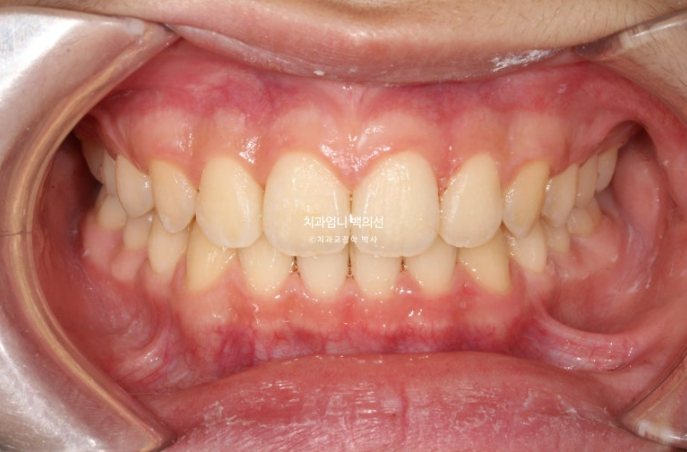

이제 전 후 비교해보겠습니다.

총 치료기간은 1년 2개월 입니다.

24.03~25.05

앞니 돌출의 개선

치근평행도는 좋고 치근흡수는 없습니다.

치아 이동속도는 빠르고 교정 부작용이 적은 것은 어린이교정의 큰 장점입니다.